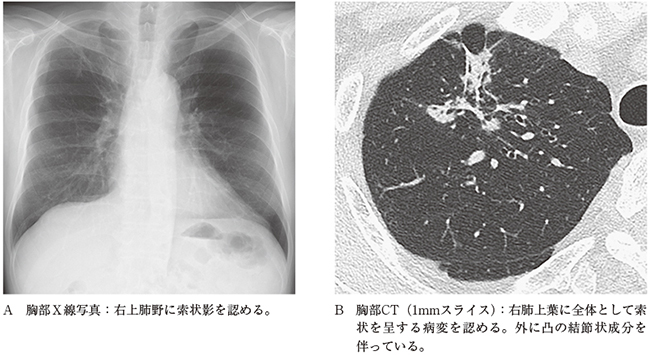

2)索状影

肺癌、特に腺癌では、炎症性瘢痕あるいは陳旧性炎症性変化に類似した索状影や線状影を呈する場合がある。特に薄層CTで外に凸の成分や索状影の周囲を縁取るようなすりガラス影がみられる場合は腺癌の可能性を疑う必要がある(図3A,B)。しかし、薄層CTでみられるようなすりガラス成分は単純X線では認識できない場合も多いことから、単純X線での索状影や線状影の評価には十分な注意を払う必要がある。

また、単純X線では腫瘍に伴う胸膜陥入像や腫瘍の末梢側に生じた部分無気肺が腫瘍本体より目立つ場合がある4)。肺癌のリスクのある状況では、陳旧性炎症としては少しでも違和感のある索状影・線状影や過去画像との比較で変化のみられる索状影、線状影については安易に良性と判断せず、CTを追加するなど慎重な対応を心掛けた方が賢明である。

図3 60歳代男性。乳頭型腺癌。